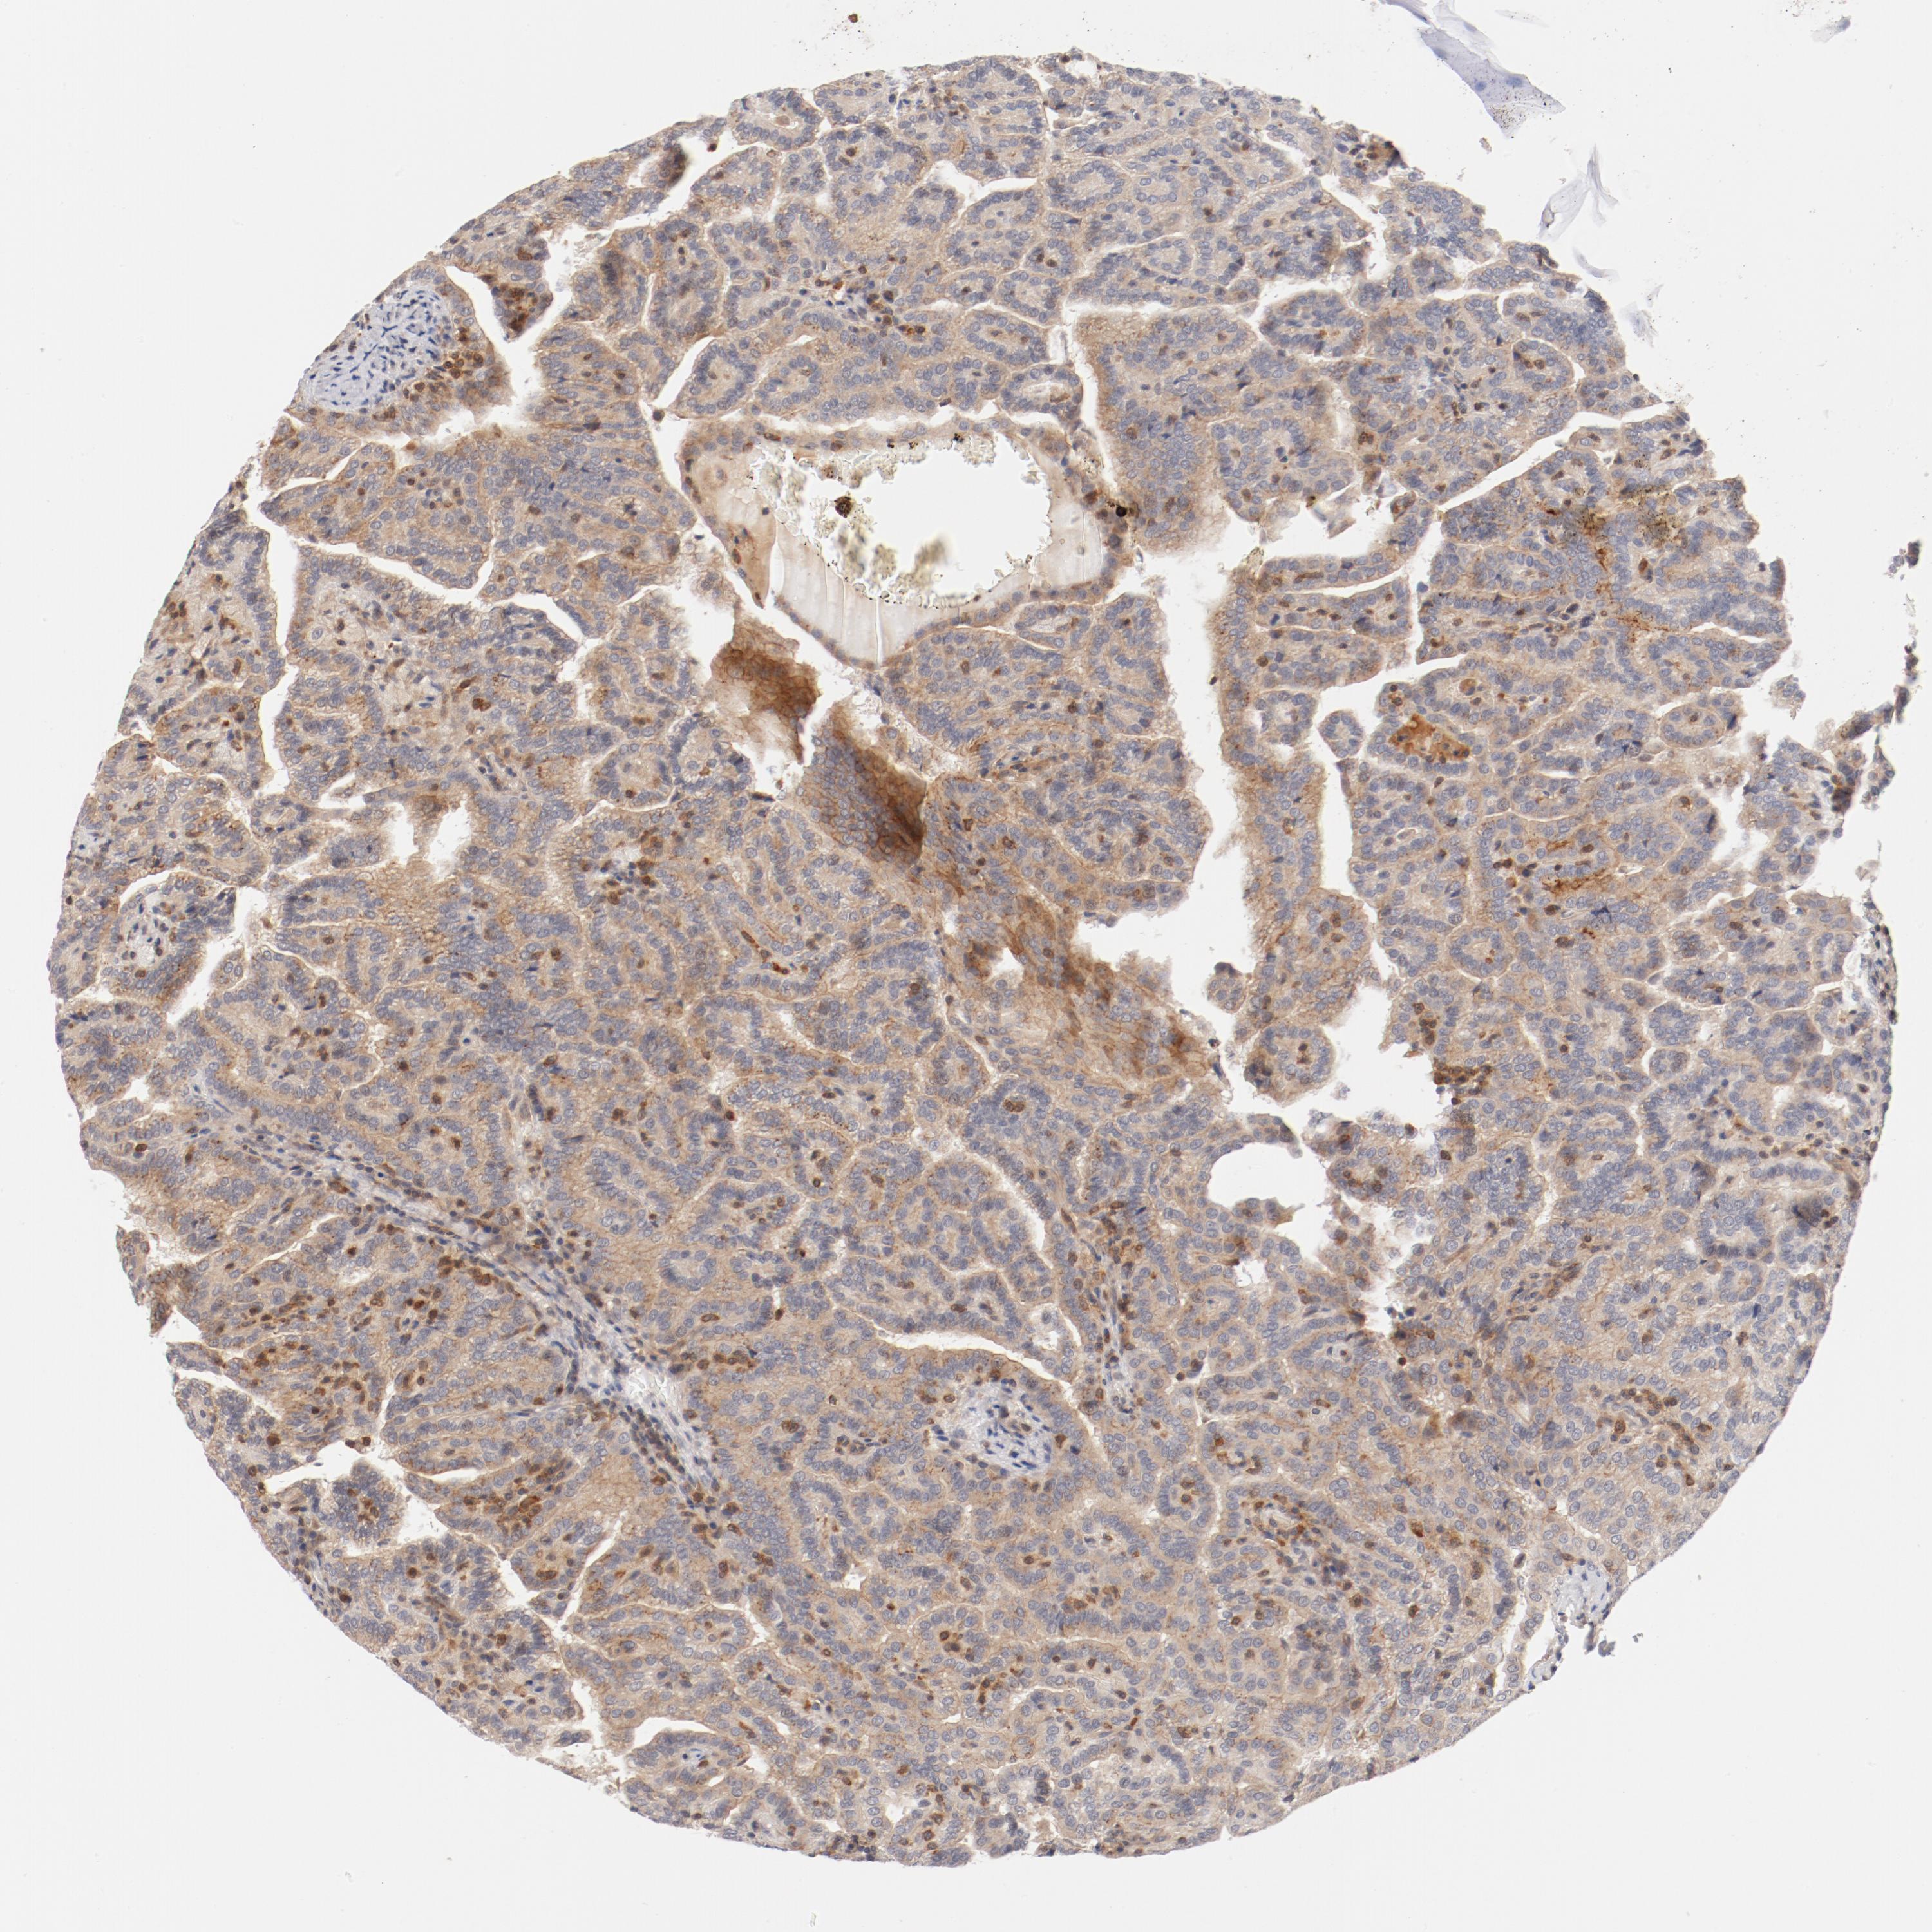

KIDNEY RENAL CLEAR CELL CARCINOMA (VALIDATION) - Interactive survival scatter ploti

The Survival Scatter plot shows the clinical status (i.e. dead or alive) for all individuals in the patient cohort, based on the same data that underlies the corresponding Kaplan-Meier plots. Patients that are alive at last time for follow-up are shown in blue and patients who have died during the study are shown in red.

The x-axis shows the expression levels (FPKM) of the investigated gene in the tumor tissue at the time of diagnosis. The y-axis shows the follow-up time after diagnosis (years). Both axes are complimented with kernel density curves demonstrating the data density over the axes. The top density plot shows the expression levels (FPKM) distribution among dead (red) and alive patients (blue). The right density plot shows the data density of the survived years of dead patients with high and low expression levels respectively, stratified using the cutoff indicated by the vertical dashed line through the Survival Scatter plot. This cutoff is automatically defined based on the FPKM cutoff that minimizes the p-score. The cutoff can be changed by dragging the vertical line or by entering a cutoff value in the square labeled "Current cut-off".

Under the Survival Scatter plot the p-score landscape (black curve; left axis) is shown together with dead median separation (red curve; right axis). Dead median separation is the difference in median mRNA expression between patients who have died with high and low expression, respectively. It is calculated as follows: median FPKM expression of dead patients with high expression - median FPKM expression of dead patients with low expression. This is intended to aid the user in visually exploring custom cutoffs and the associated p-scores and dead median separation.

Individual patient data is displayed and can be filtered by clicking on one or more of the category buttons on the top of the page. Categories describing expression level and patient information include: high, low, alive, dead, female, male and tumor stages. The scale of the x-axis can be toggled between linear and log-scale by clicking on the "x log" button. Mouse-over function shows TCGA ID, patient information and mRNA expression (FPKM) for each patient.

& Survival analysisi

Kaplan-Meier plots summarize results from analysis of correlation between mRNA expression level and patient survival. Patients were divided based on level of expression into one of the two groups "low" (under cut off) or "high" (over cut off). X-axis shows time for survival (years) and y-axis shows the probability of survival, where 1.0 corresponds to 100 percent.

ZNF267 is not prognostic in Kidney Renal Clear Cell Carcinoma (validation)

: 16.25

Average pTPM 14.9

Number of samples 100